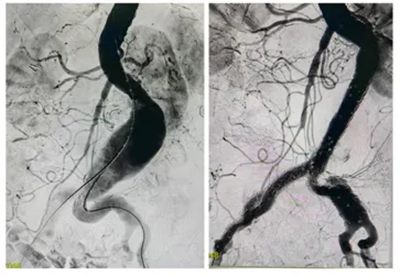

情况危急,血管外科团队迅速为刘奶奶安排了“腹主动脉覆膜支架腔内隔绝术”。

▲ 术中造影,腹主动脉局部瘤样扩张,行“覆膜支架隔绝”封堵良好

这是一种微创手术,仅用2小时就成功拆除了这颗“炸弹”。术后第3天,刘奶奶就能下地自如活动,腹痛也消失了,顺利康复出院。